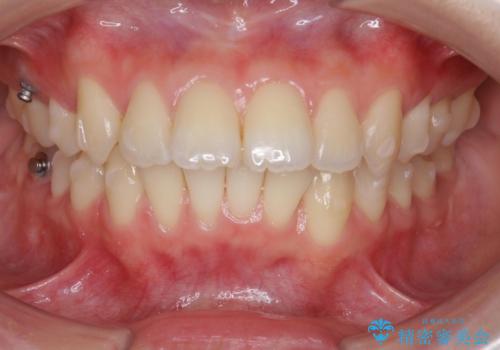

突き出た前歯の改善!マウスピースで再矯正

- 5年前にワイヤー矯正治療を終了したが、突き出たように見える前歯の仕上がりが気に入らず、再矯正治療を希望され来院されました。

マイクロインプラントを用いた遠心移動とIPRを行うことによる前歯の突出感の改善をマウスピース矯正治療で計画します。

突出していた前歯の角度が大きく改善し、審美的な仕上がりに満足いただくことができました。